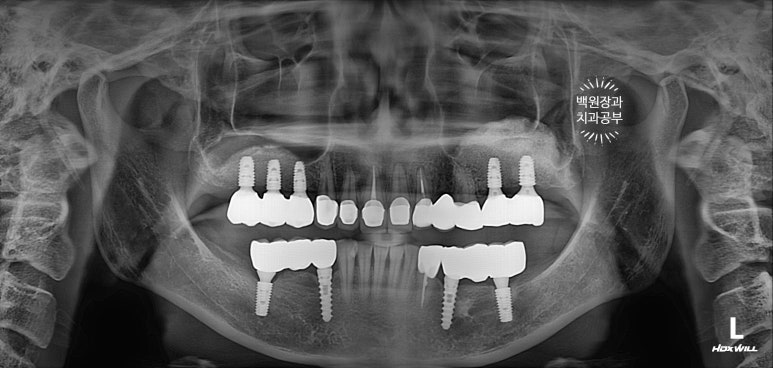

앞니와 어금니를 완성해두고 치과용 파노라마 엑스레이를 찍어봅니다.

새로 만들어진 보철물이 경계도 자연스럽게 잘 형성되어있고, 잇몸뼈와 조화롭게 완성이 되었네요.

정말... 다시봐도 상악동 뼈이식술이 아주 적절히 잘 되어 딱 필요한만큼만 되어있네요. ㅎㅎ 이럴때 정말 뿌듯합니다. (변태같나요!?)

가장 보람을 느끼게 되는 보철물 완성 후 치과용 파노라마 사진입니다.

정갈하게 치아가 완성되었네요... 이런 맛에 치과의사 하는 것이 아닌가 싶습니다.

뼈가 너~무 얇아 임플란트를 해드릴 수 없었던 송곳니 부위는 지르코니아 브릿지로 제작함으로써 자연스럽게 마무리 되었습니다.